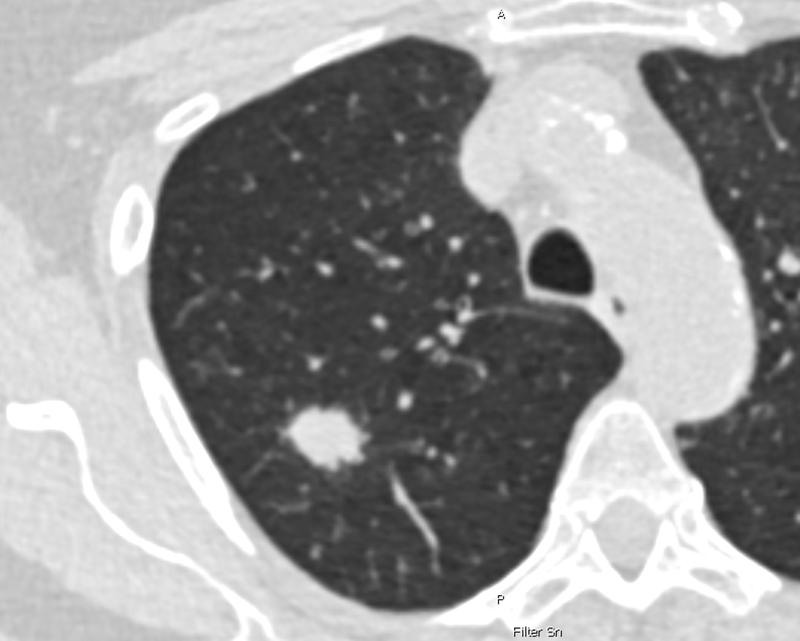

Jedes Jahr wird in Deutschland bei rund 57.000 Menschen Lungenkrebs diagnostiziert – mit oft tödlichem Ausgang, weil die Erkrankung typischerweise zu spät entdeckt wird. Voraussichtlich ab April 2026 soll ein neues Früherkennungsprogramm starten, das bei Menschen mit hohem Lungenkrebsrisiko mittels Computertomografie (CT) überprüft, ob verdächtige Veränderungen der Lunge vorliegen. Bisher ist geplant, dass das Lungenkrebs-Screening Personen zwischen 50 und 75 Jahren angeboten wird, die – vereinfacht gesagt – über 25 Jahre stark geraucht haben**.

Verglichen wurden die Ergebnisse mit den Auswahlkriterien, die dem geplanten Lungenkrebs-Screening zugrunde liegen sollen und die ausschließlich das Alter und die Rauchhistorie berücksichtigen („NELSON-Score“). Alle Personen, denen anhand einer der beiden Scores ein hohes Lungenkrebsrisiko attestiert wurde, erhielten im Rahmen der Studie im Abstand von einem Jahr zweimal ein Niedrigdosis-CT. Verdachtsfälle wurden in interdisziplinären Fallkonferenzen überprüft und bei Bestätigung eine Behandlung eingeleitet.